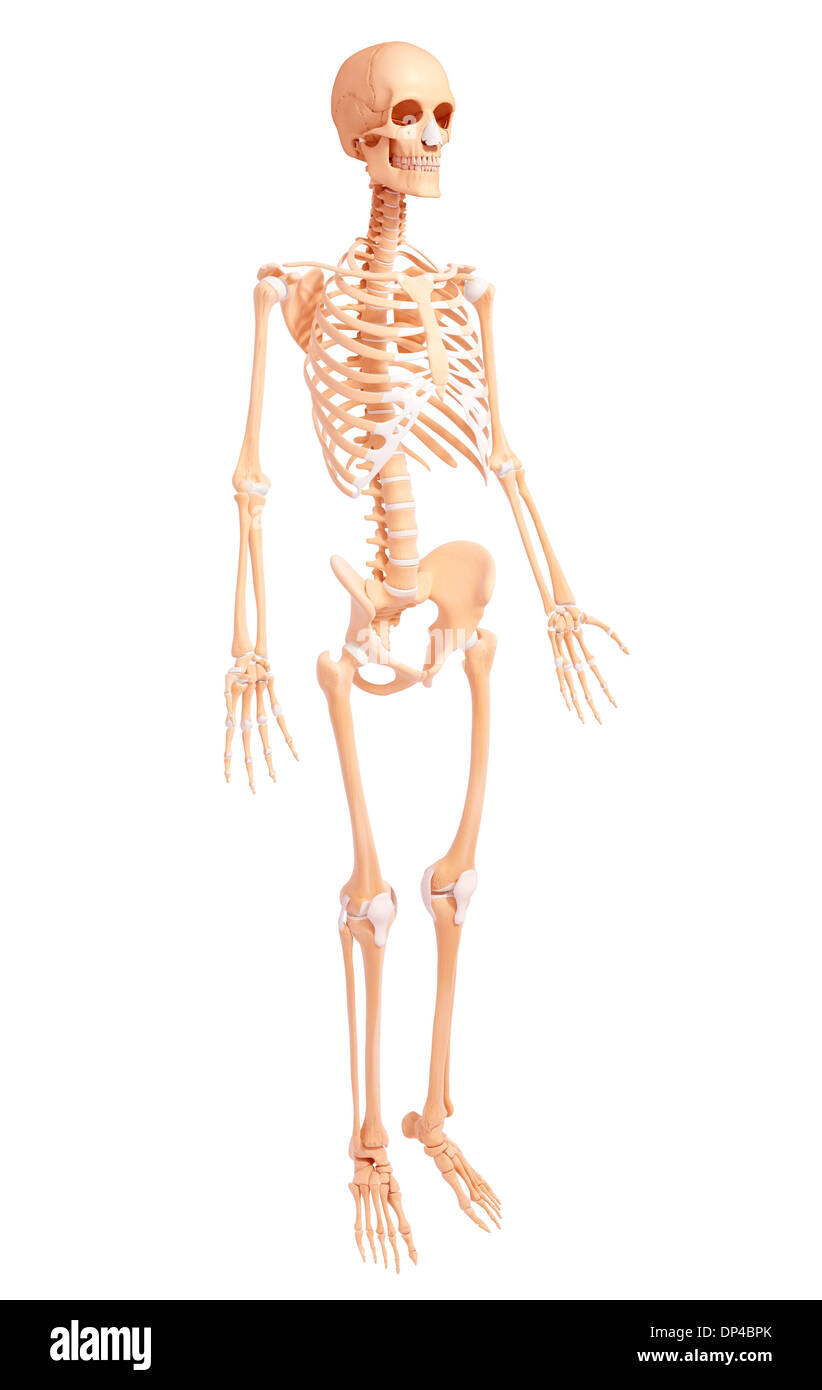

Human Skeleton, artwork Banque D'Imageshttps://www.alamyimages.fr/image-license-details/?v=1https://www.alamyimages.fr/human-skeleton-artwork-image65250603.html

Human Skeleton, artwork Banque D'Imageshttps://www.alamyimages.fr/image-license-details/?v=1https://www.alamyimages.fr/human-skeleton-artwork-image65250603.htmlRFDP4BPK–Human Skeleton, artwork